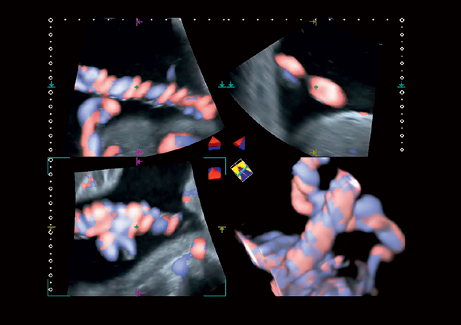

• STIC - исследование сердца плода в режиме объёмной визуализации

• 3D Color - цветное 3-х мерное изображение

• STIC Color - цветная объёмная визуализация сердца плода

• MPR - функция мультипланарной реконструкции для визуализации исследуемой области в 3-х ортогональных плоскостях

• Трехмерная эхография в реальном времени с использованием специализированных 4D датчиков;

• Программа анализа сердца плода в трех проекциях в реальном времени 4D Stick;